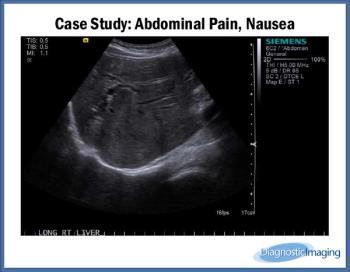

Case History: Female patient in early 60s with abdominal pain and nausea.